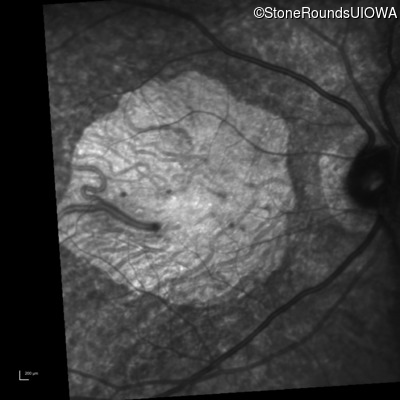

Infrared Fundus Photograph - Left - 20/200 sc

Exemplar